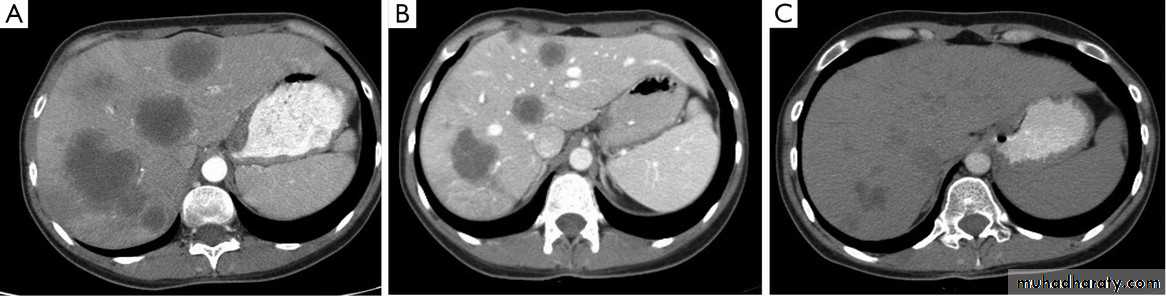

Secondary metastasis in the liver

Multiple rounded hypo density areas of different density , shape & different size .

Pattern of enhancement is either uniform , target or bulls eye pattern .

Hepato megaly .

Hydatid cyst within the liver

Secondary metastasis within the liver